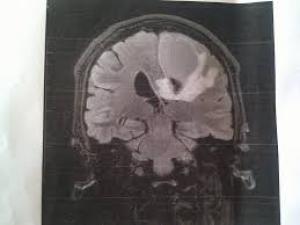

Специалисты отмечают, что такой рак формируется преимущественно у людей в диапазоне 50-65 лет. В таком возрасте нужно с должным вниманием относиться к собственному здоровью, при необходимости проходить обследование, в основе которого - МРТ головы. Такое обследование помогает выявлять любые новообразования в головном мозге на начальных стадиях, чтобы своевременно приступить к соответствующему курсу и существенно понизить стоимость лечения рака в Израиле.

На сегодня существует 2 информативных и очень доступных метода: КТ и МРТ. Как раз по причине распространенности томографов возросла выявляемость опухолей мозга.